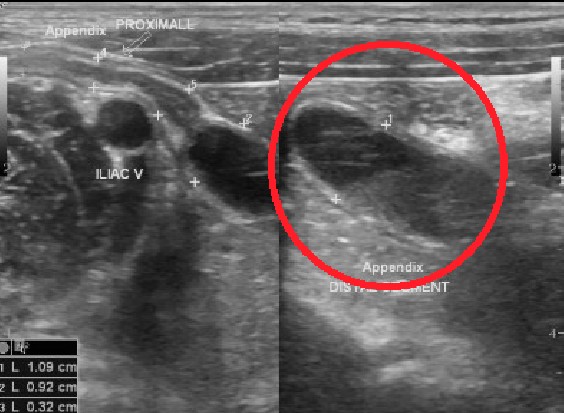

진단은 이렇게 합니다.

- 문진·진찰 + 혈액검사(CRP/백혈구)

- 영상검사

- 성인: 조영증강 CT가 진단 정확도와 대체 진단 파악에 강점 -> 대부분 CT를 찍는다고 보시면 됩니다.

- 소아/임신: 초음파 먼저, 임신에서 초음파가 애매하면 MRI가 안전하고 유용

- 필요한 경우에만 촬영하고, 방사선 노출을 최소화합니다.

- 참고로, CT가 보급되기 전에는 오른쪽 아랫배가 아프면 일단 수술방에 가서 배를 열고 시작했다고 합니다. 이때 맹장염이 아니고 게실염이나 장염인경우에도 그냥 맹장을 떼버리고(나중에 염증이 생길수도 있으니..) 배를 닫았다는 말도 들었습니다.

- CT로 진단 확정(소아·임신은 초음파→필요 시 MRI)